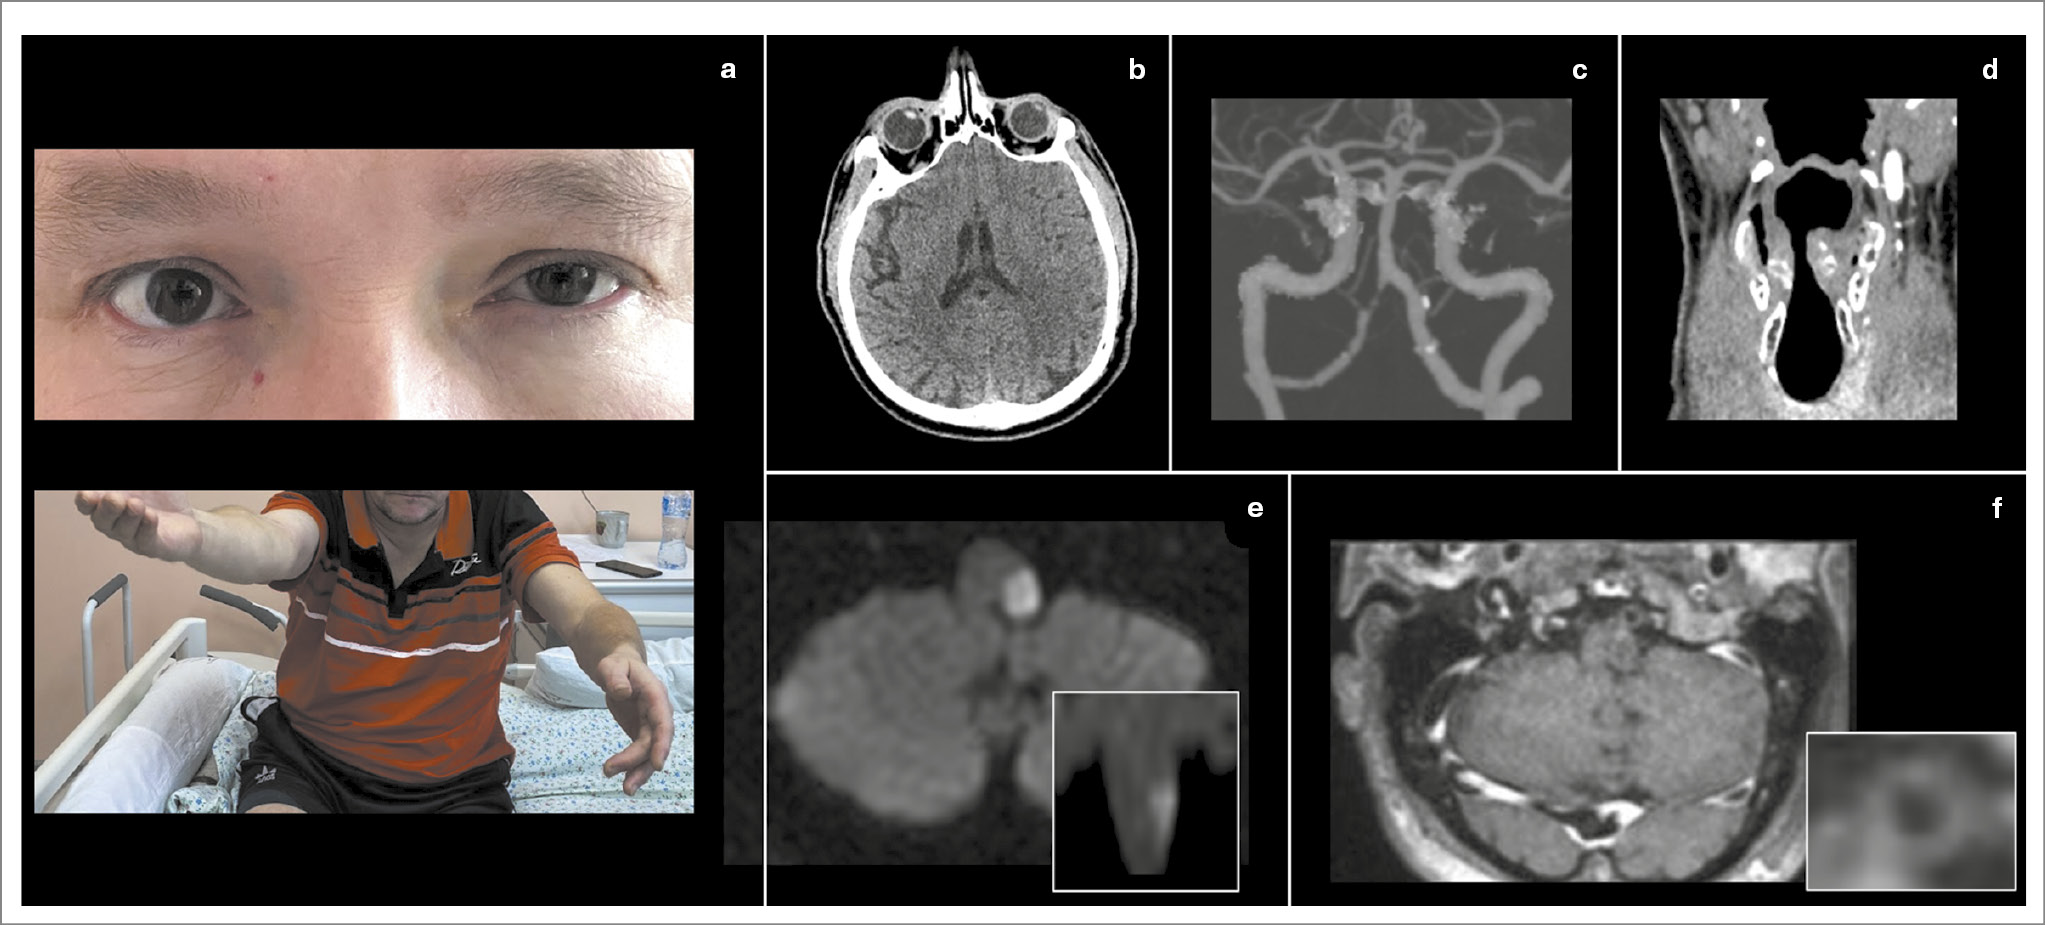

Рис. 3. Клинический пример типичного ЛМИ. Пациент 61 года. В 2021 г. перенес инфаркт миокарда, принимает клопидогрел. 25 февраля 2024 г. жена заметила, что у пациента невнятная речь, вскоре появились неустойчивость при ходьбе, тошнота и рвота. Поступил через 6 ч от начала заболевания с жалобами на головокружение. При поступлении выявлены синдром Горнера слева (a, нижнее изображение), горизонтально-торсионный нистагм, направленный вправо, положительный OLD-тест слева (a), легкая дизартрия и дисфагия, снижение болевой и температурной (в больше степени) чувствительности в правой половине тела, выраженная туловищная атаксия. Выполнена КТ головного мозга, визуализированы формирующаяся зона снижения плотности в латеральных отделах продолговатого мозга слева (c2), кальцификаты в проекции IV сегмента левой позвоночной артерии (c1), а также выраженная содружественная девиация глаз влево (b). При проведении КТА выявлен выраженный стеноз IV сегмента левой позвоночной артерии (d), а также медиальное смещение левой голосовой связки, свидетельствующее о ее парезе (e). На следующий день дисфагия прогрессировала до выраженной, установлен назогастральный зонд. Через 2 нед по данным бронхоскопии с оценкой глотания сохранялась дисфагия 1-й cтепени, парез верхней трети гортани и левой голосовой складки. Через месяц выполнена МРТ (Т2-взвешенное изображение) головного мозга, визуализирована зона кистозных изменений в латеральных отделах продолговатого мозга слева (c3).